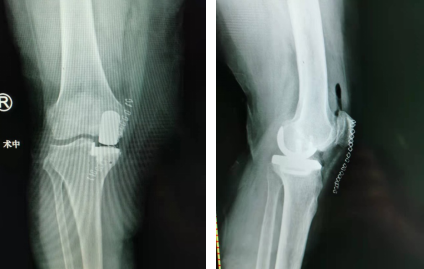

关节科邱东新医生接诊后对阿姨进行了详细的检查,发现孙阿姨右下肢比左下肢要短2cm,双膝关节内翻畸形,右膝关节内侧关节间隙压痛明显,已经严重影响日常生活,符合手术指征。如果孙阿姨早些年来治疗的话,只需要矫正腿的畸形,并不需要手术治疗。

在和阿姨及家属仔细沟通后,结合患者实际病情,邱医生决定对其进行右膝关节单髁置换术。右膝关节单髁置换术相较于传统手术来说,创伤更小,只需要对磨损的关节进行修补、不会损伤关节内韧带,保留了关节的自然活动,风险更低,术后两三天患者即可下地活动。

通过仔细的术前设计,手术团队术中在右前膝内侧小心切开,显露关节后,发现内侧关节软骨磨损严重,骨质增生,在清理好骨赘之后,对胫骨内侧进行修补,在测试过屈伸活动正常后,手术顺利结束。

术后第三天,孙阿姨就能扶着拐杖下地走路了,除了刀口轻微的酸麻外,手术前膝盖内侧的疼痛感已经明显消失。